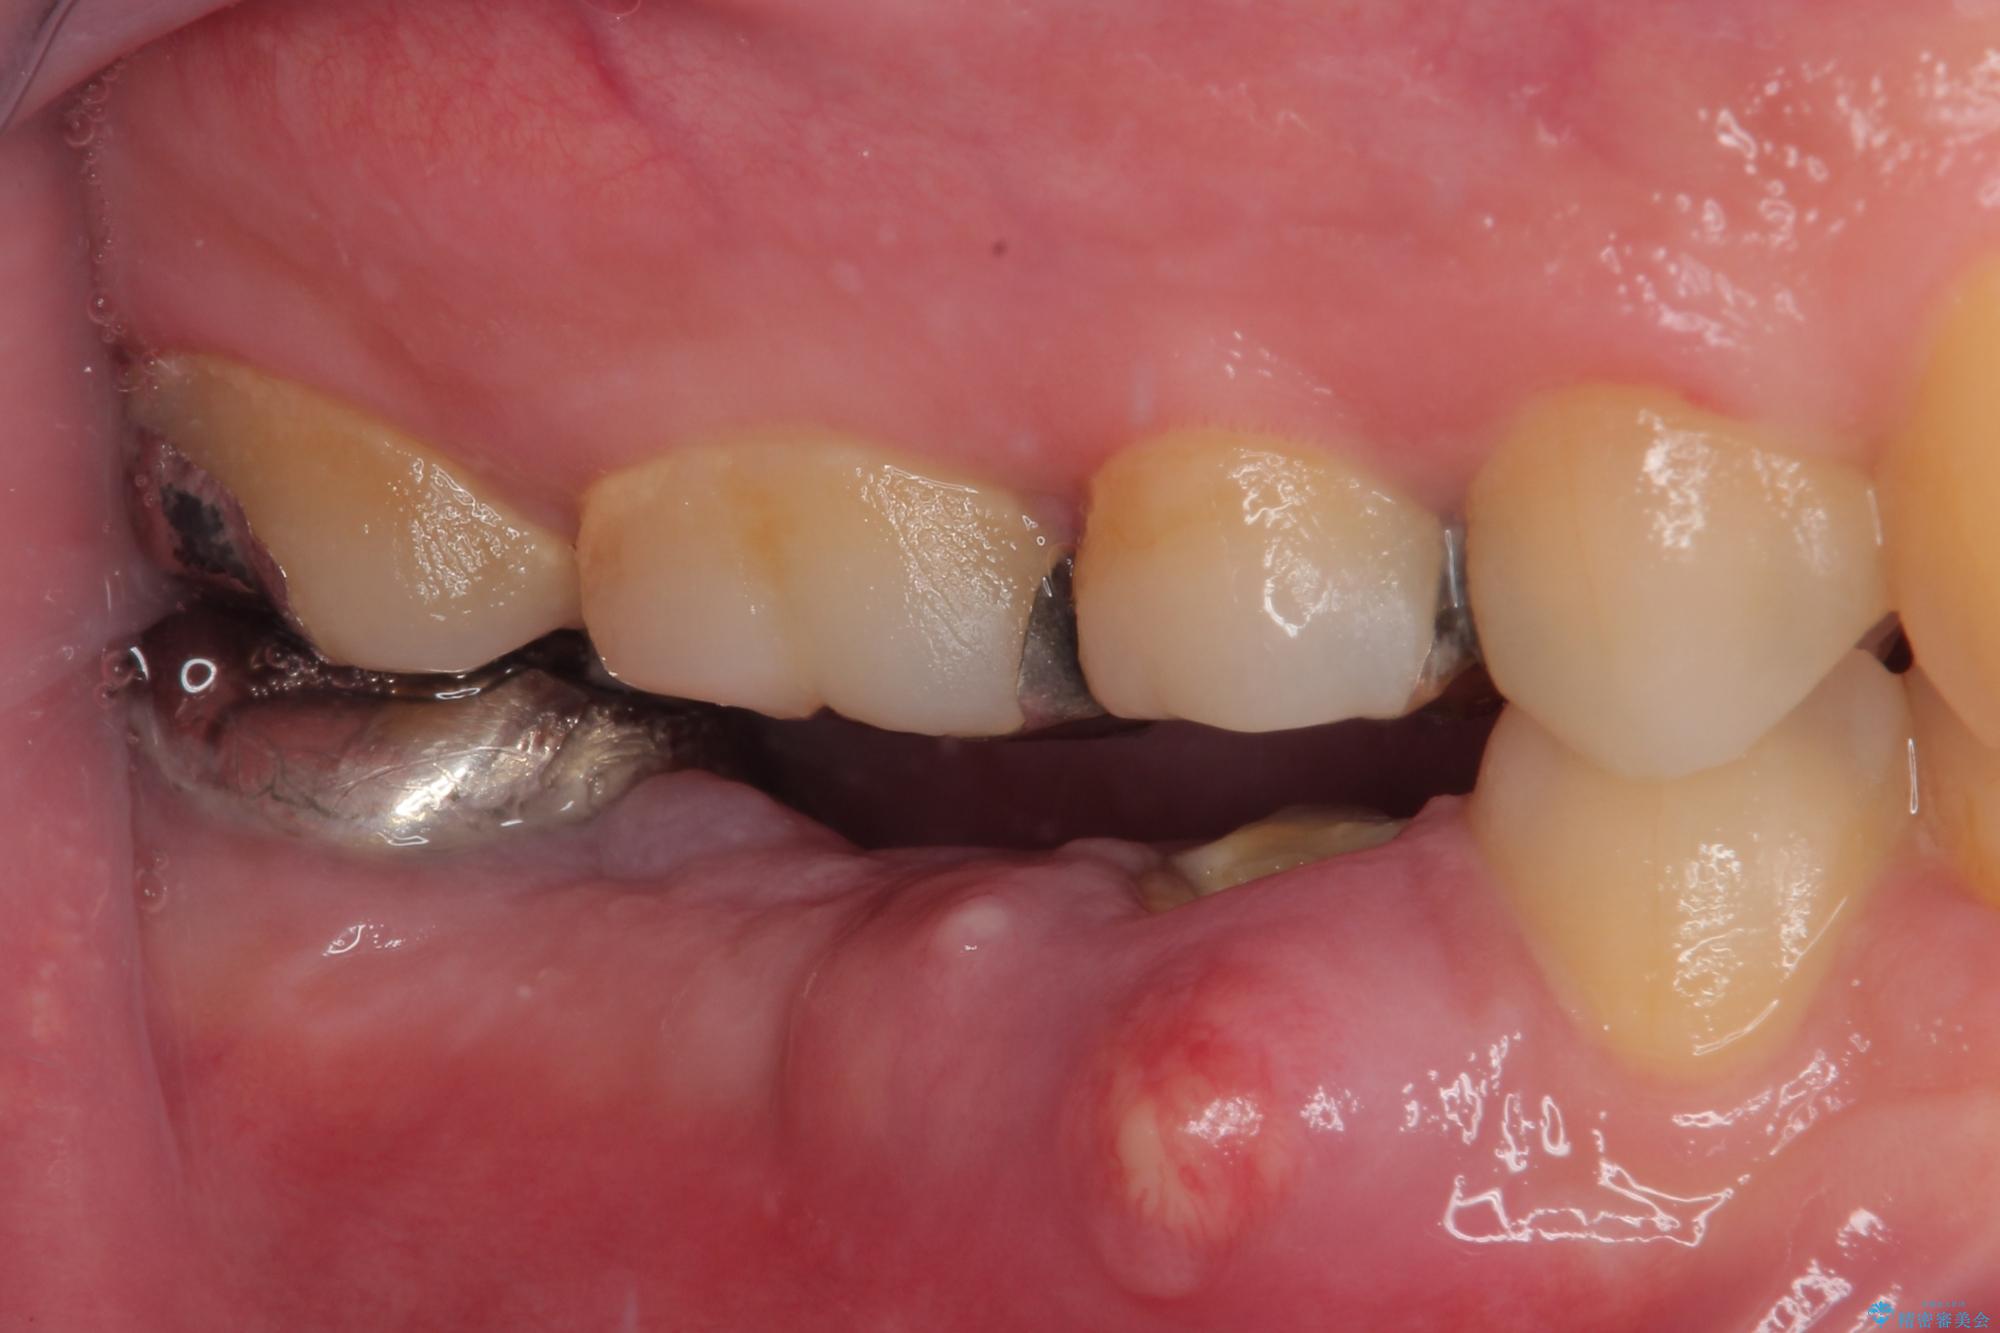

咬合力が非常に強い患者様であり、2歯欠損のブリッジ(しかも大臼歯は失活歯)は歯根破折のリスクが高すぎると判断し、抜歯部および欠損部に対して、インプラントによる補綴治療を行うこととしました。

抜歯即時埋入部と後方の欠損部は、即日荷重(インプラント埋入と同時に仮歯を装着すること)が可能な安定値が得られましたが、長い期間欠損した状態で過ごすと、欠損部に舌を押し当てる癖が発現してしまい、舌からの側方圧でインプラントが脱離するリスクが著しく高まってしまうため、即日荷重は行いませんでした。

おかげでインプラントは無事に生着し、僅か4ヶ月で治療を終えることができました。